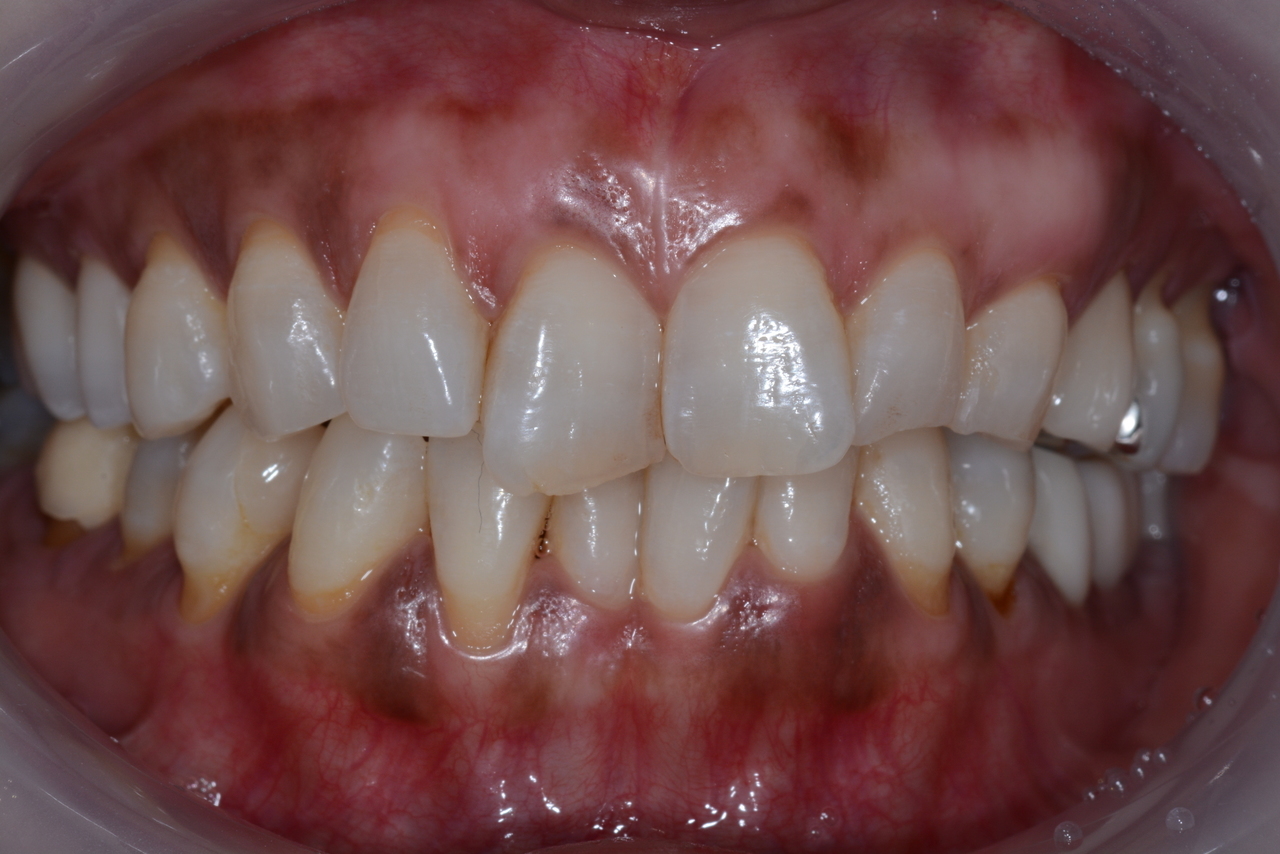

10日後白い薄皮が剥がれて、

ピンク色の歯茎に変わります。